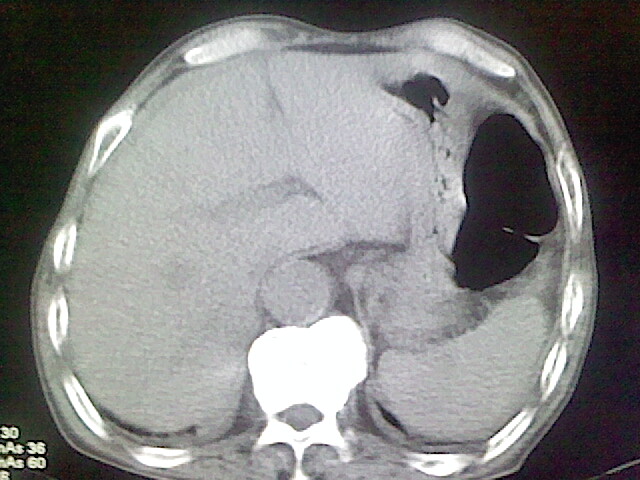

以下是引用zsl6918在2008-8-28 16:49:00的发言:[br]双肺炎性病灶,食管狭窄估计与心房增大压迫所致。

以下是引用xulianj在2008-8-28 20:36:00的发言:[br]慢支肺气肿伴感染,右上肺陈旧性结核;食道建议胃镜检查。

以下是引用wqs571018在2008-8-28 21:18:00的发言:[br]慢支继发感染,右上肺陈旧性结核;食道建议胃镜检查。